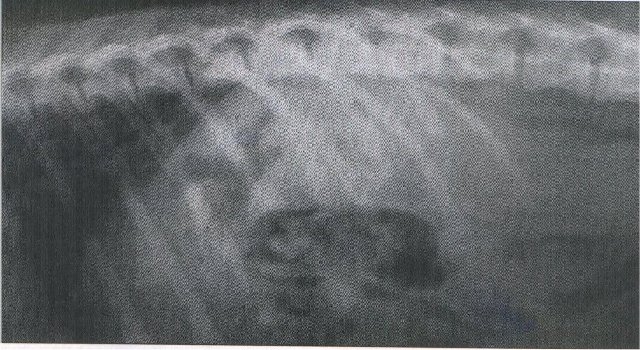

Lateral survey radiograph of dog with portosystemic shunt. Note the small liver

and forward displacement of the gastric shadow (photograph courtesy of P.

Watson, University of Cambridge).